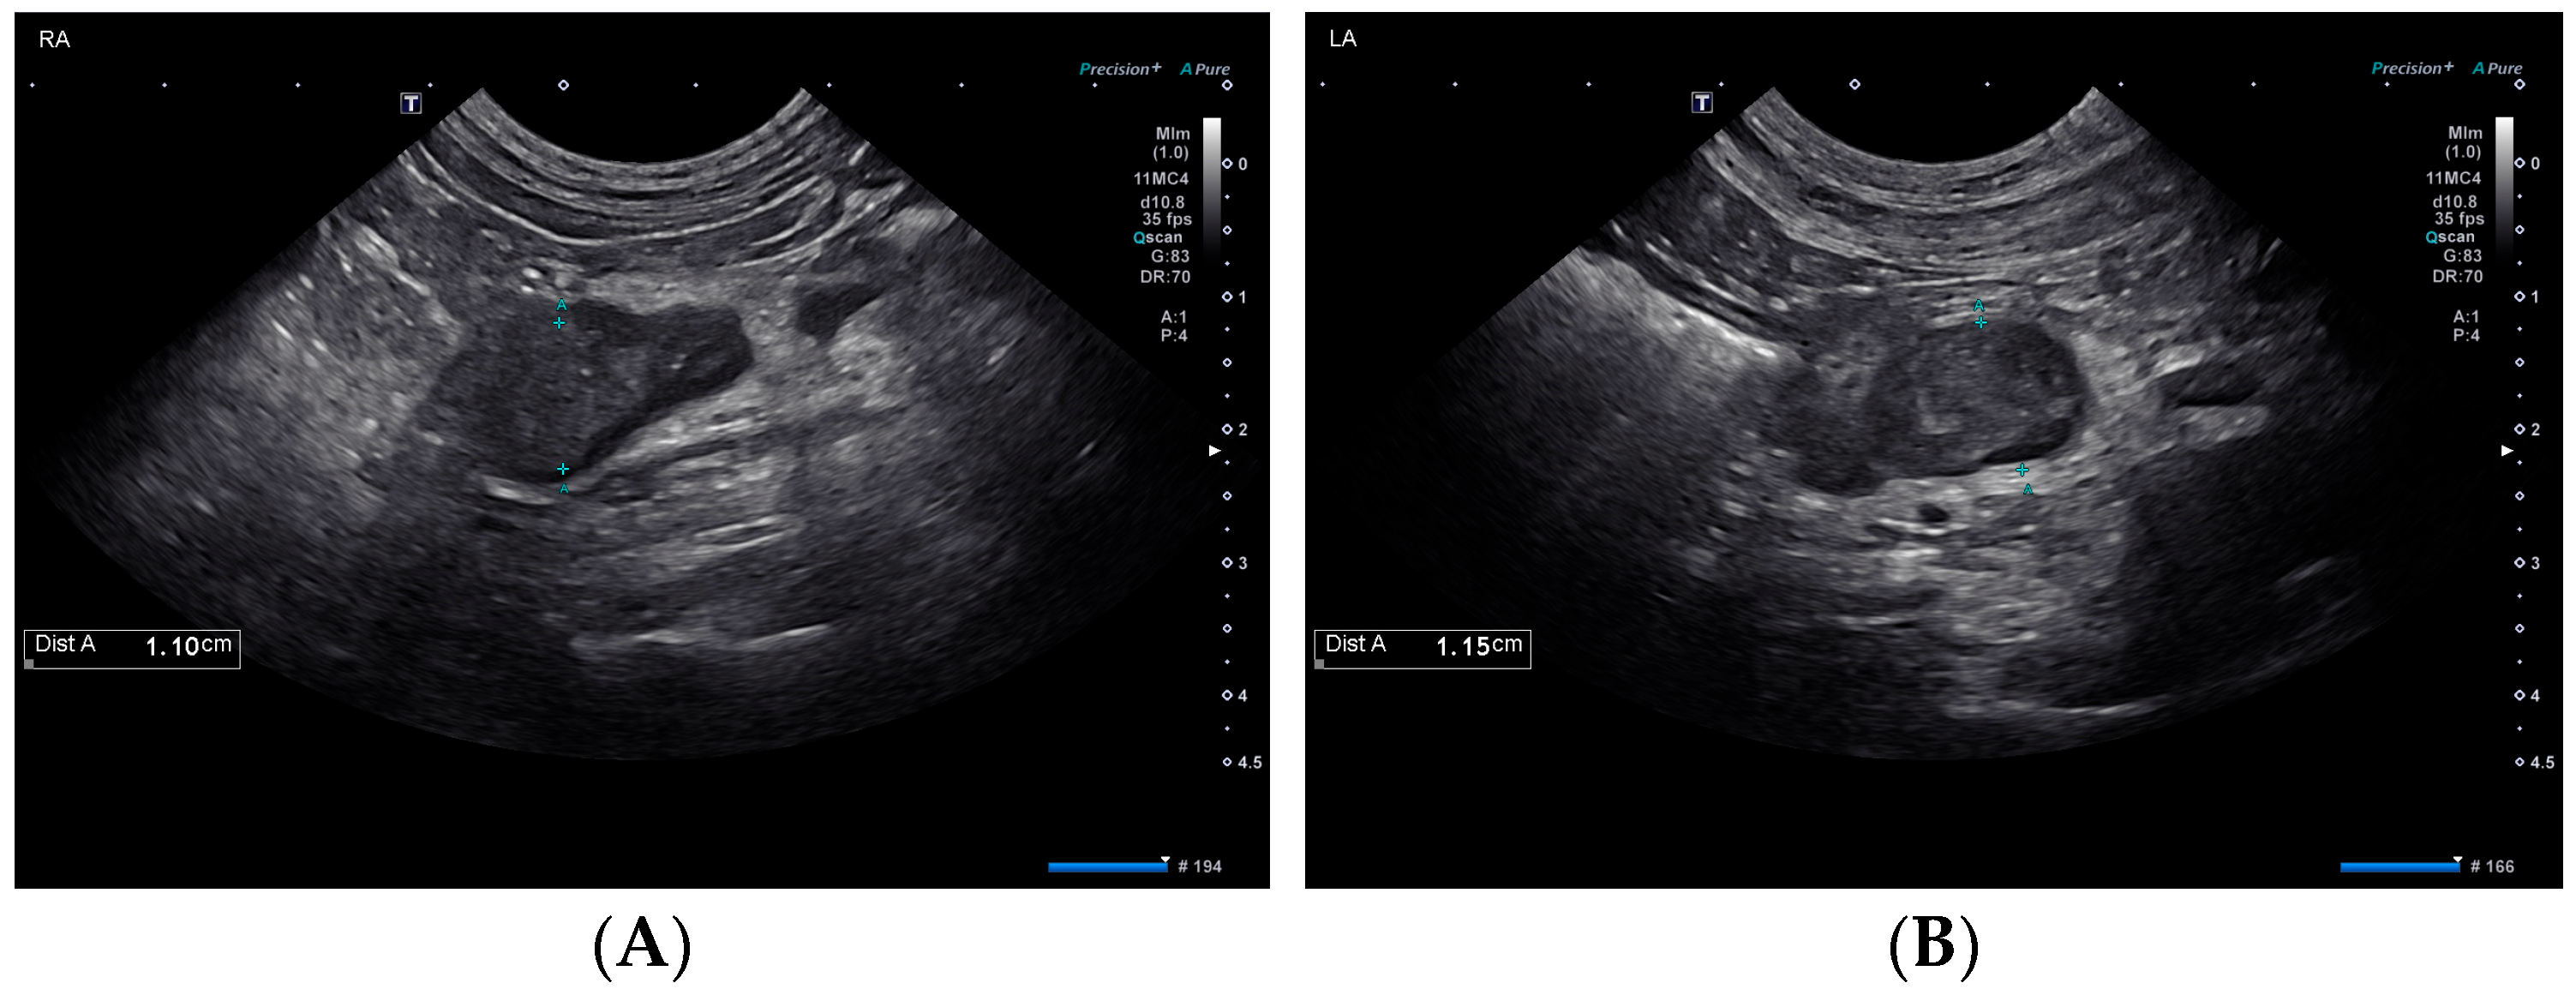

Also on day 1, thoracic radiographs were obtained and interpreted by a board-certified radiologist as unremarkable. An abdominal ultrasound performed by a board-certified radiologist found mildly hyperechoic hepatic parenchyma with few small, hypoechoic nodules, mildly enlarged hepatic and periportal lymph nodes, and changes consistent with gall bladder wall edema suggestive of an acute hepatopathy. The urinary bladder was distended, and the proximal urethra was moderately thickened. The urinary catheter was in place during the ultrasound. The adrenal glands were enlarged bilaterally with the left adrenal gland measuring 1.1 cm in diameter with a slightly heterogeneous architecture, and the right adrenal gland measuring 1.1 cm in diameter with the cranial aspect expanded by an ill-defined rounded hypoechoic region measuring 1.1 cm in diameter (Figure 1).

Figure 1.

Ultrasonographic findings of the right (A) and left (B) adrenal glands on day 1.

The dog in this case report was diagnosed with amanitin intoxication and subsequent hepatic dysfunction based on the detection of a trace concentration of alpha-amanitin in urine. She recovered and was diagnosed with typical hypoadrenocorticism (HA) 25 days post-initial presentation. The chronology of these events suggests that alpha-amanitin intoxication might have resulted in an adrenocortical injury leading to HA. Given the normal plasma aldosterone concentration on day 1, the patient likely did not have aldosterone deficiency at this time, but this result does not rule out pre-existing cortisol deficiency. Hypoadrenocorticism could have developed in this dog independent of the intoxication caused by idiopathic destruction, immune-mediated or metastatic disease or an ischemic event [11,12,13]. However, the dog’s initial and subsequent diagnostic work-up revealed no evidence of embolic disease or neoplasia, making these differentials unlikely. The initial ultrasound evaluation of the dog revealed mild bilateral adenomegaly, with measurements greater than typically reported for dogs with HA [14,15]. This finding could represent active adrenalitis or may be an incidental finding as the adrenal glands appeared and measured similarly at recheck ultrasound examination on day 25. Without histopathological evaluation of this dog’s adrenal glands, the definitive cause for the development of HA remains a conjecture, but amanitin intoxication is a top differential.